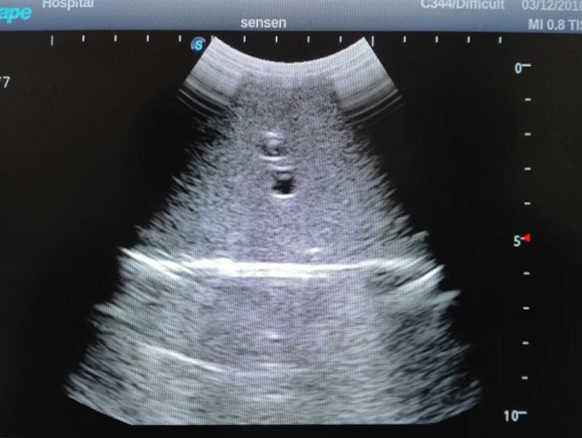

1) Ideal for trainings like ultrasound-guided abdominocentesis with visible ascites flowing out, ultrasound-guided femoral artery & venous puncture

2) High quality ultrasound image with clear structures like gallbladder, liver, intestines, arteries and veins etc.